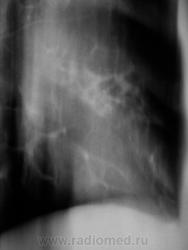

Контроль через 1 месяц после противовоспалительной терапии.